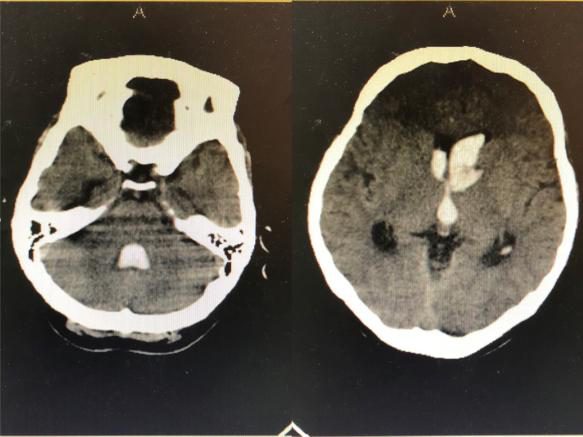

2018年9月3日,一位突发昏迷的患者被推到了神经外科病区。头颅CT提示脑出血破入脑室,合并急性脑积水,必须立即手术。当医生和患者家属提到手术时候,患者家属确实欲言又止,犹豫不决,询问患者家属后得知患者父母已故,也没有子女,唯一的亲人就是姐姐,患者与姐姐都没有工作,仅靠着姐姐的低保维持生活,如今听到要手术,姐姐不知如何是好。时间不等人,如果再拖延时间患者可能因急性脑积水失去生命,神经外科王刚副主任告诉患者家属先做手术抢救生命,钱以后再说,手术顺利进行,术后患者转入重症监护室。

得知患者经济困难后,崔健科主任积极与医院沟通,当大家来到患者仅有几平方米的“家”中,看到他们极其贫困的生活状况时,不由得潸然而泪,决定帮助患者渡过难关。主动与患者家属联系,告知他们安心看病,生命永远是第一位的。经过22个日日夜夜与死神博弈,在神经外科团队的全力救治及精心护理下,患者逐渐意识转清,一侧的肢体力量逐渐恢复,并于10月10日步行出院。